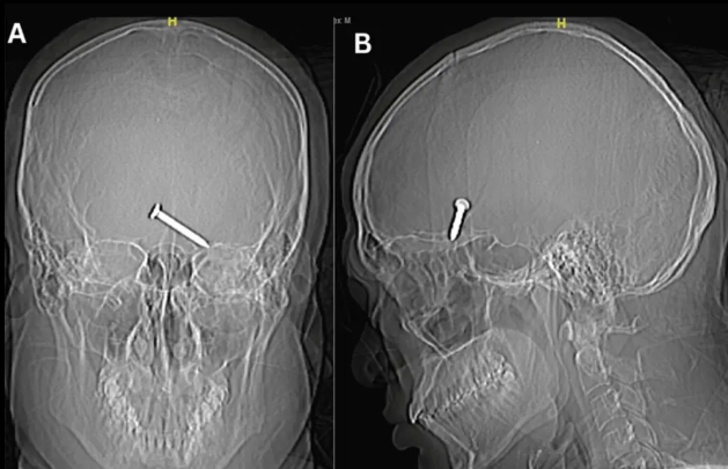

Röntgen görüntüleri, 3,2 cm büyüklüğündeki çivinin, hareket ve konuşma için hayati önem taşıyan beyninin ön lobunun derinliklerine saplandığını gösterdi.

Cureus tıp dergisinde yayınlanan araştırmaya göre, sol gözünün yan kantusunda (iki göz kapağının birleştiği yerde) yaralar ve sol yörünge tavanında ve tabanında kırıklar da vardı. Çalışma, çivinin bir şekilde hayati arterleri ve sinirleri ıskaladığını ve uzun vadeli herhangi bir hasardan kurtulduğunu söyledi. Hasta mucizevi bir şekilde hayatta kalırken görme yeteneğini de kaybetmedi.